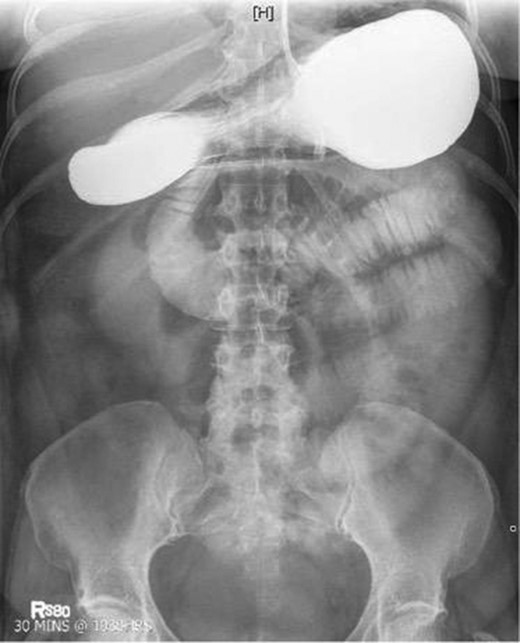

Laboratory studies were remarkable for leukocytosis, and an elevated lactate that improved with hydration (Fig. 1), while urinalysis was unremarkable. Abdominal CT scan obtained at this time demonstrated a partial SBO in the mid-small bowel as well as inflammation and thickening of the duodenum. A small bowel series was ordered, and showed high grade SBO (Figs 2–5).

Fluoroscopic barium study demonstrating oral contrast agent progression through the small bowel at 5 h after ingestion. Dilated bowel loops can be visualized throughout the abdomen, and transit time is delayed. Impression—high-grade distal small bowel obstruction.